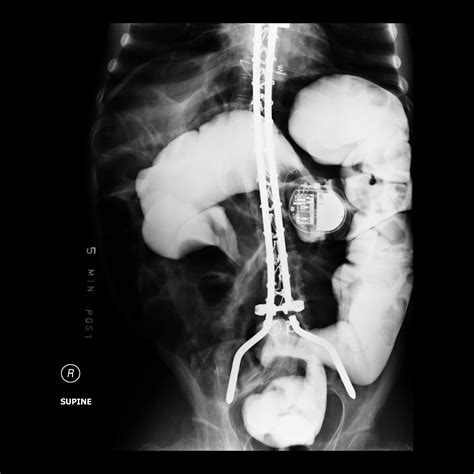

The Birdbeak Sign is a distinctive radiographic appearance seen on abdominal X-rays or CT scans. It is characterized by a tapered, beak-like appearance of the sigmoid colon, which indicates a twist or volvulus. This sign is crucial because it helps radiologists and gastroenterologists identify the presence of a sigmoid volvulus, which is a medical emergency requiring immediate intervention.

Flexible sigmoidoscopy is a minimally invasive procedure that allows for the direct visualization of the lower colon and rectum. It involves the use of a flexible, lighted tube called a sigmoidoscope, which is inserted through the anus to examine the interior of the colon. This procedure is particularly useful in diagnosing conditions such as polyps, inflammation, and, importantly, sigmoid volvulus.

Interpreting the Birdbeak Sign During Flexible Sigmoidoscopy

During a flexible sigmoidoscopy, the presence of a Birdbeak Sign can be confirmed by visualizing the twisted sigmoid colon. The sigmoidoscope allows for a direct view of the colon, enabling the gastroenterologist to assess the extent of the twist and the condition of the colonic mucosa. This direct visualization is crucial for confirming the diagnosis and planning the appropriate management strategy.